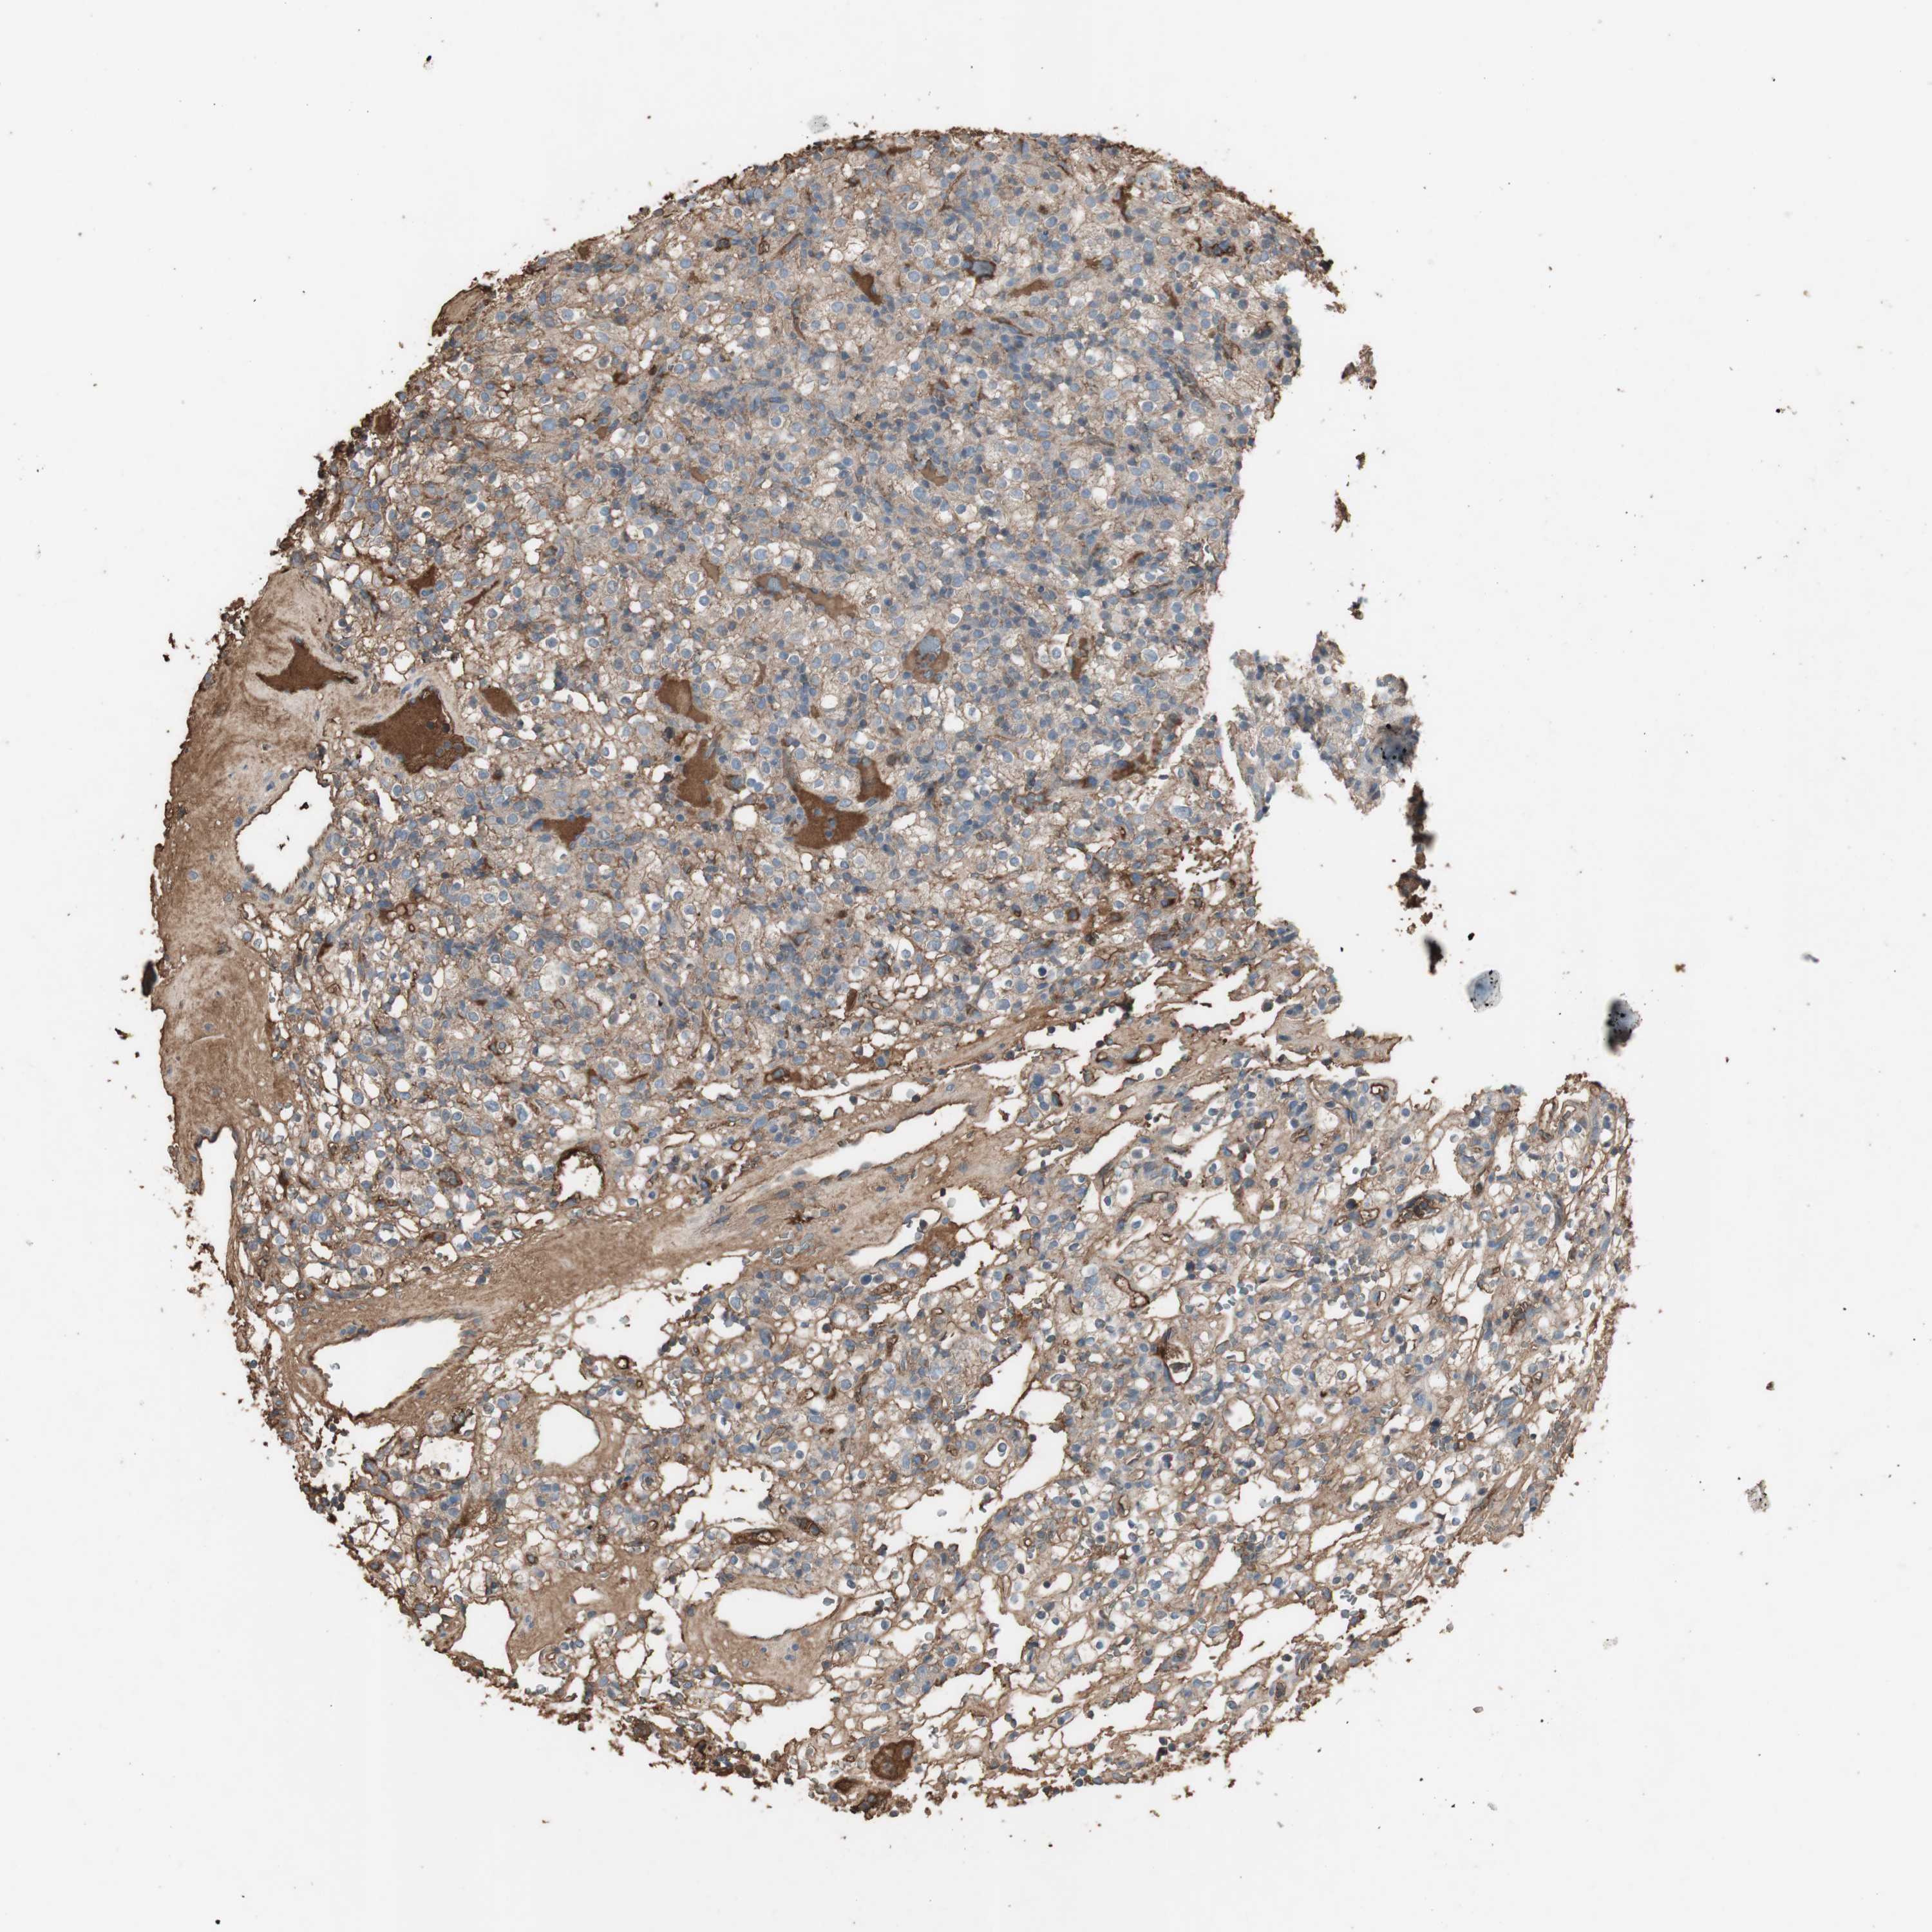

CANCER RENAL CANCER Show tissue menu

KICH TCGA KIRC TCGA KIRC VALIDATION KIRP TCGA PROTEIN RCC CPTAC PROTEIN EXPRESSION

Renal cancer

Kidney renal clear cell carcinoma